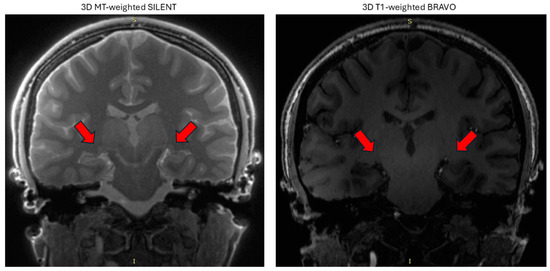

| 3D BRAVO T1-W | 3D MT-W SILENT | |

| FOV [cm] | 22 × 22 | 17.6 × 17.6 |

| Slice thickness [mm] | 1.0 | 0.8 |

| TE [ms] | 2.6 | 0.0 |

| TR [ms] | 6.6 | 257 |

| TI [ms] | 450 | not applicable |

| Matrix size | 288 × 288 | 224 × 224 |

| NEX | 1 | 3 |

| Flip Angle | 12 | 2 |